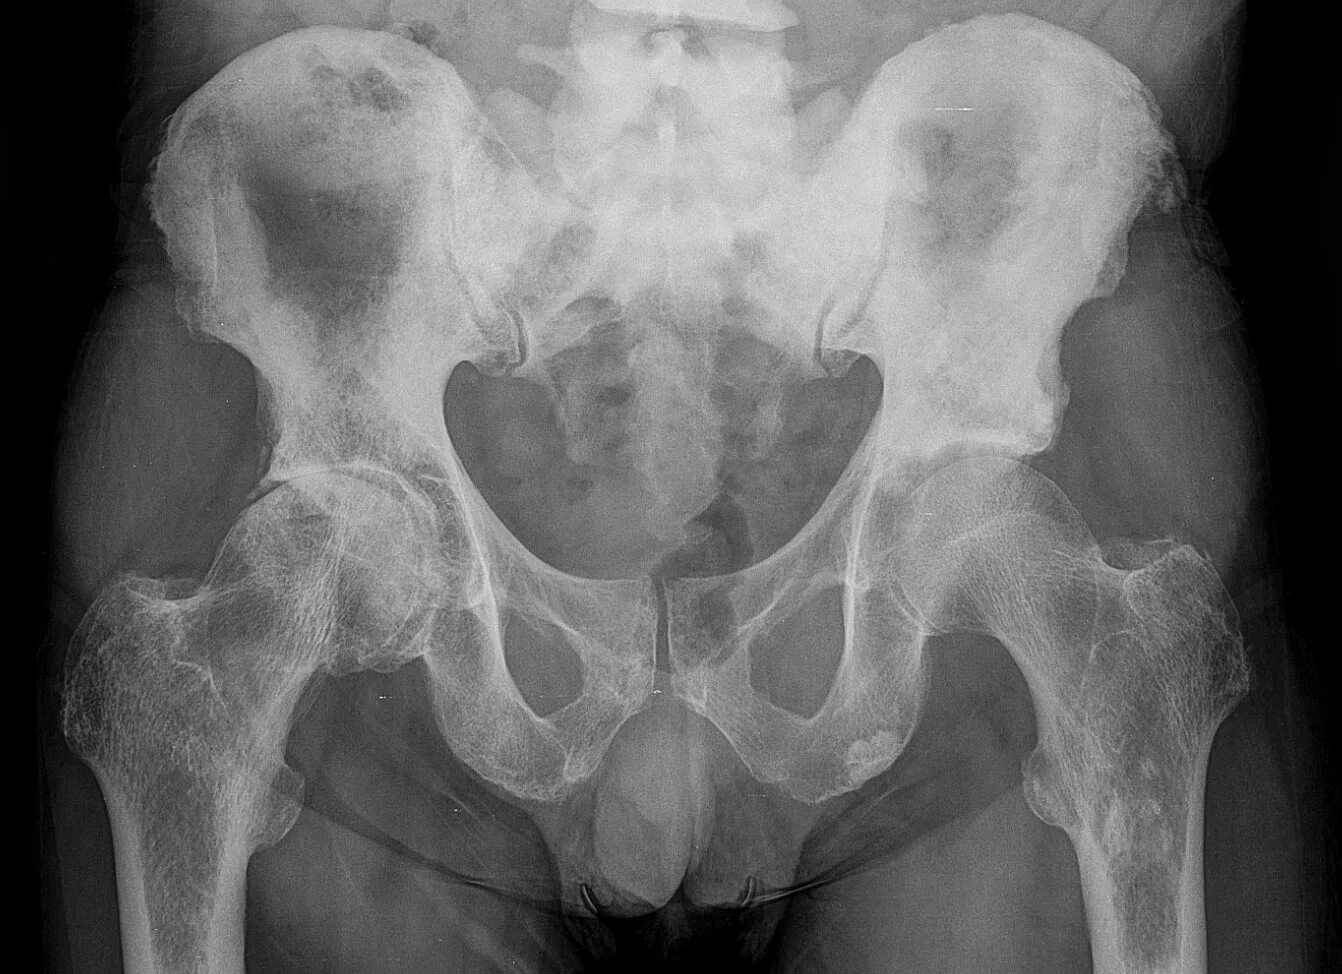

Метастазы в костях при раке предстательной железы